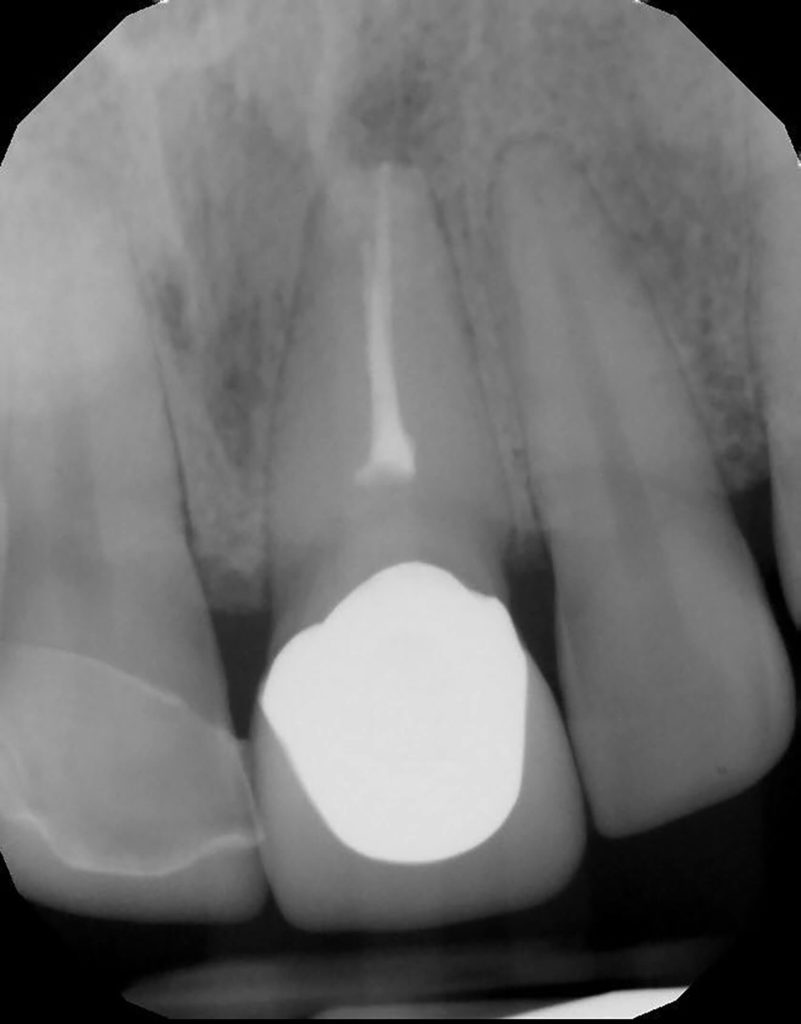

Fun retreatment. Patient had RCT on 9, which was retreated by another endodontist 5 years ago. Patient developed pain and swelling in the area. CBCT revealed a transported canal with a perforation. I was able to locate the canal and hopefully save the tooth!